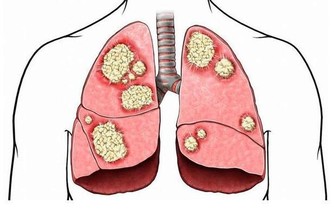

4、腸胃疾病

慢性胃炎、胃或十二指腸潰瘍病、返流性食管炎、膽囊炎等疾病,可促使胃酸增多。例如十二指腸粘膜可以釋放某些激素,而當這種功能衰退時,也可能導致胃酸分泌增加。